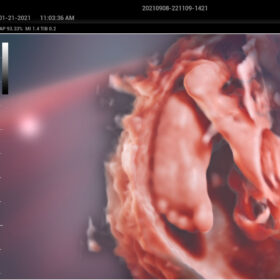

Comprehensive Imaging Solutions Powered by ZST+

The ZST+ platform is a remarkable advancement, marking a significant evolution in ultrasound technology. It revolutionizes the processing of ultrasound metrics, moving away from the traditional beam-forming approach to channel data-based processing. This breakthrough eliminates the longstanding trade-off challenges between spatial resolution, temporal resolution, and tissue uniformity. The result is outstanding image quality, providing limitless imaging solutions with continuous enhancements.

- Smart Scene 3D – Full Stack smartness obstetric solution empowered by ZST+. Comprehensive 3D/4D OB imaging solution with comprehensive fetal parts coverage.

One Key for favorite fetal part imaging, reducing manual adjustment - Smart Face – Automatic removal of occlussions over fetal face with one click